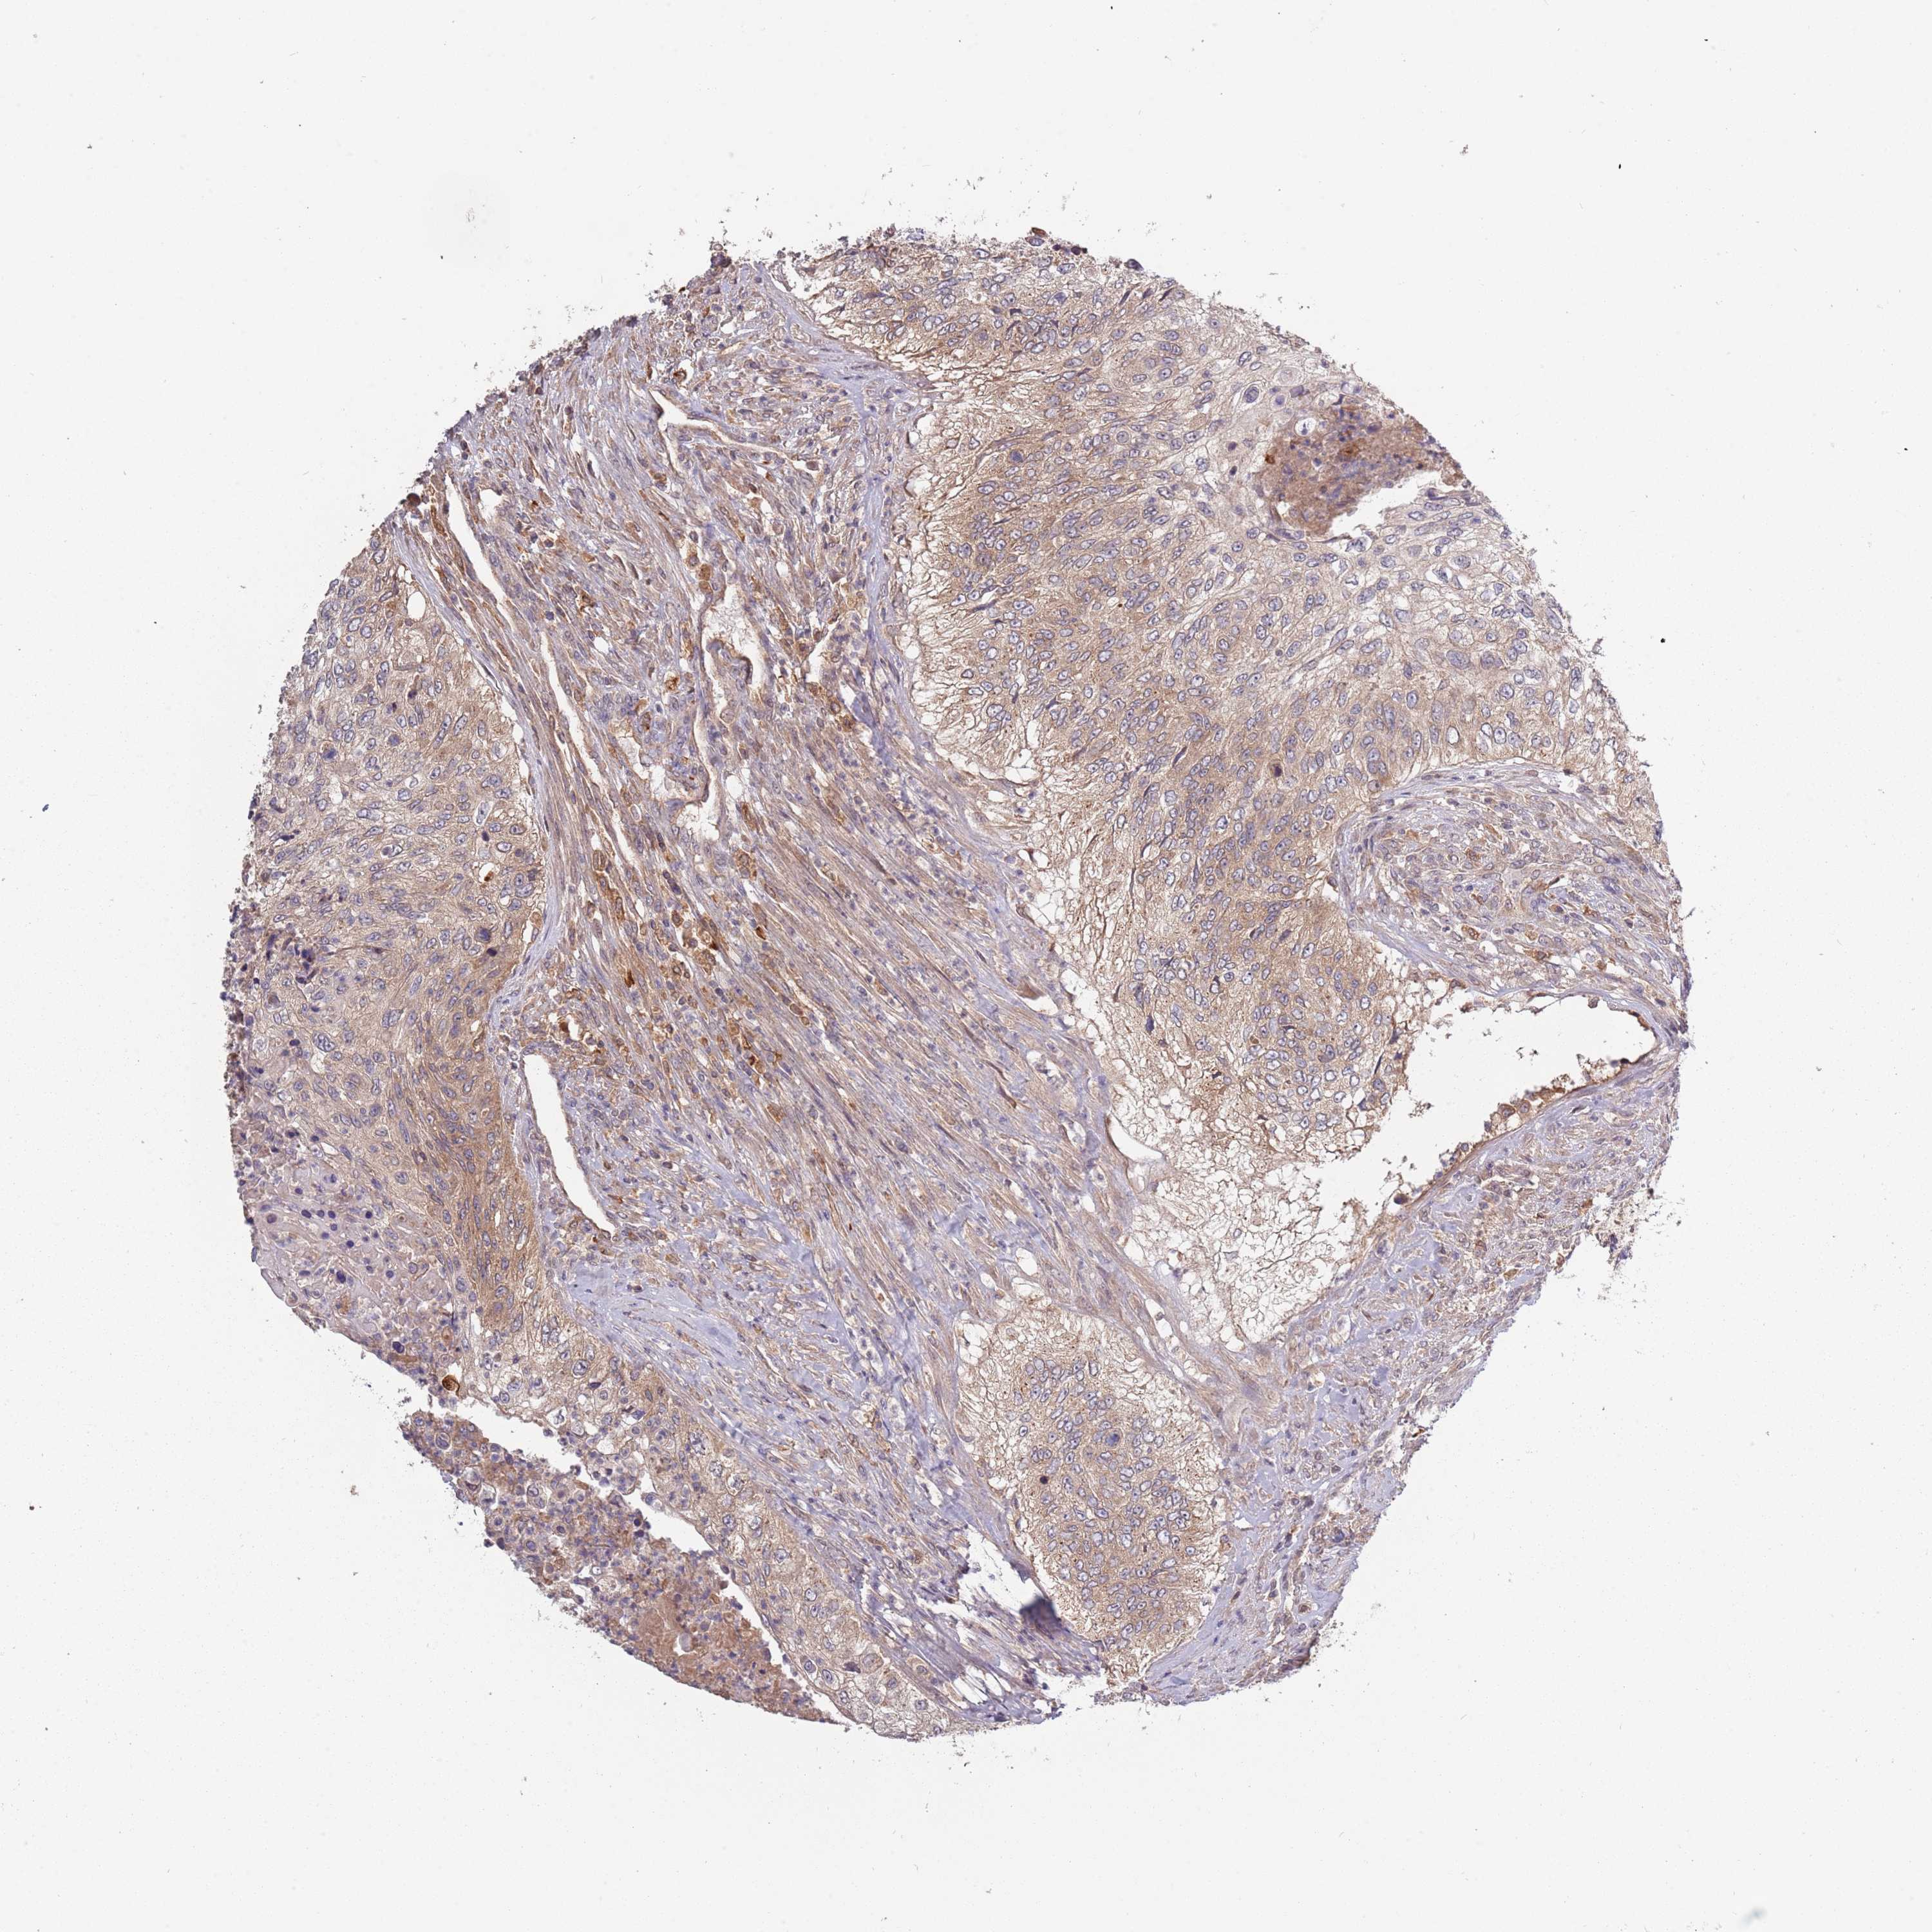

UROTHELIAL CANCER - Protein expressioni

A mouse-over function shows sample information and annotation data. Click on an image to view it in a full screen mode. Samples can be filtered based on level of antibody staining by selecting one or several of the following categories: high, medium, low and not detected. The assay and annotation is described here.

Note that samples used for immunohistochemistry by the Human Protein Atlas do not correspond to samples in the TCGA dataset.

Antibody stainingi

Antibody staining in the annotated cell types in the current human tissue is reported as not detected, low, medium, or high, based on conventional immunohistochemistry profiling in selected tissues. This score is based on the combination of the staining intensity and fraction of stained cells.

Each image is clickable and will lead to virtual microscopy that enables deeper exploration of all samples and also displays staining intensity scores, fraction scores and subcellular localization as well as patient and tissue information for each sample.

Antibody HPA044365

Staining

High

Medium

Low

Not detected

Intensity

Strong

Moderate

Weak

Negative

Quantity

>75%

75%-25%

<25%

None

Location

Nuclear

Cytoplasmic/membranous

Cytoplasmic/membranous,nuclear

Urothelial carcinoma, Low grade

Urothelial carcinoma, High grade

Urothelial carcinoma, NOS